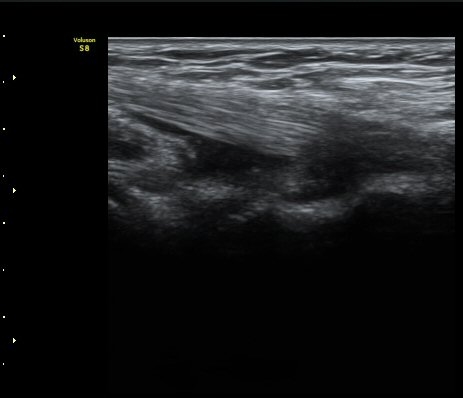

ÆÈ²ÞÄ¡ µÚÂÊ °üÀý¸éÀ¸·ÎºÎÅÍ 2.5cm ¾Æ·¡¿¡¼­ ¿ä°ñ°ü°ú ô°ñ °æ°èºÎ¸¦ Ⱦ´Ü¸éÀ¸·Î

°Ë»çÇÏ´Ï ¿ä°ñµÎ¿¡ ºÎÂøµÈ À̵ιڱ٠ÈûÁÙÀÌ °üÂûµÈ´Ù(±×¸² 9). Á¾´Ü¸é°Ë»ç¿¡¼­µµ

À̵ιڱ٠ÈûÁÙ°ú ¿ä°ñµÎ°¡ ¶Ñ·ÈÈ÷ °üÂûµÈ´Ù(±×¸² 10).